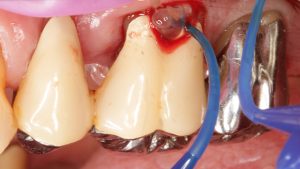

Hyaluronsäure (HA) ist seit mehreren Jahren erfolgreich in der Medizin für die Behandlung von Wunden, chronischen Narben und Verbrennungen im Einsatz 6. Doch welche...